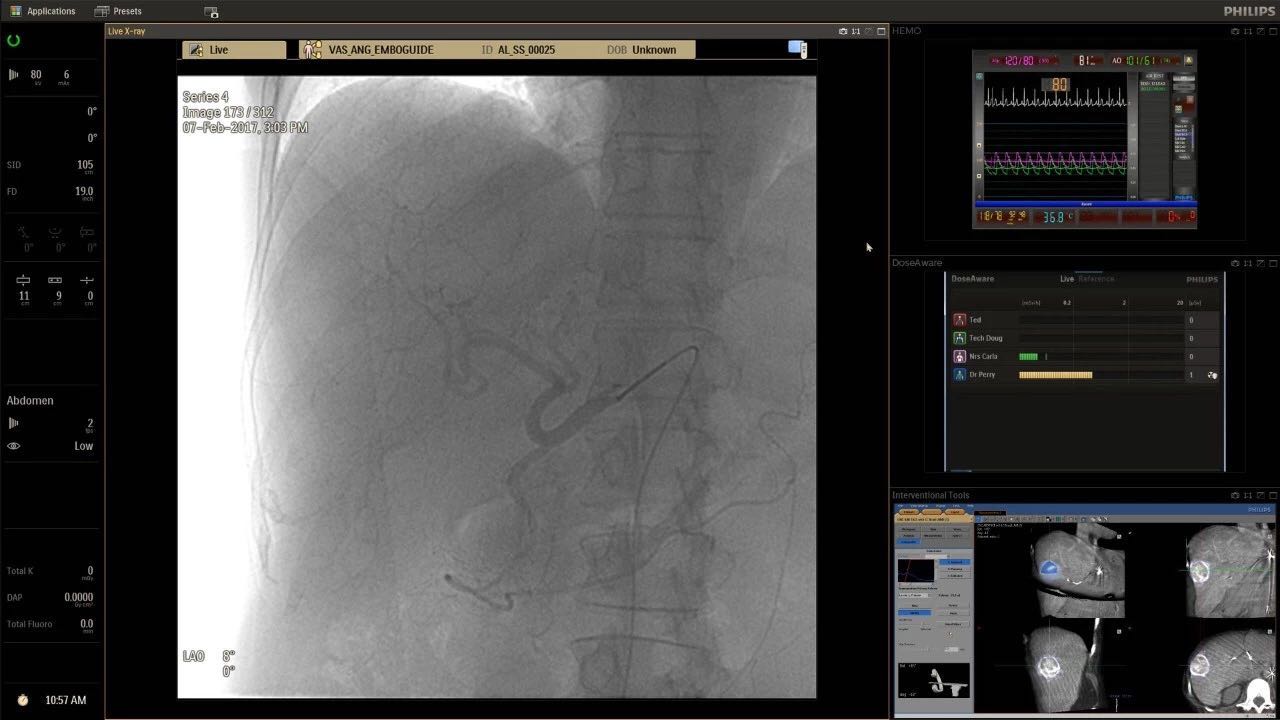

帶有FlexArm的Azurion 7 C20 包含一系列創(chuàng)新技術(shù),使臨床醫(yī)生可以更輕松地在整個(gè)患者身上進(jìn)行二維和三維成像。當(dāng)臨床醫(yī)生移動(dòng)系統(tǒng)時(shí),圖像光束自動(dòng)保持與患者的對(duì)準(zhǔn),允許更一致的可視化并使他們能夠?qū)⒆⒁饬性谥委熒稀?/span>

(FlexArm C型臂可以沿著工作臺(tái)的兩側(cè)提供偏心成像。這允許醫(yī)生在左臂或右臂上進(jìn)行徑向進(jìn)入病例,完全或部分伸展,而無(wú)需移動(dòng)患者或樞轉(zhuǎn)桌子。X射線束與手臂保持對(duì)齊,以促進(jìn)其整個(gè)長(zhǎng)度的平滑導(dǎo)航,而無(wú)需進(jìn)行持續(xù)調(diào)整。)

(FlexArm在不少于8軸的情況下旋轉(zhuǎn),從而創(chuàng)建幾乎無(wú)限的靈活性來(lái)執(zhí)行成像,從頭部到腳部在左側(cè)和右側(cè)進(jìn)行2D和3D可視化。圖像光束保持與患者對(duì)齊,允許在旋轉(zhuǎn)或角度期間更好地可視化解剖結(jié)構(gòu)。使用Axsys運(yùn)動(dòng)控制系統(tǒng)輕松操作支架。)